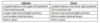

Anatomy Flashcards

(229 cards)